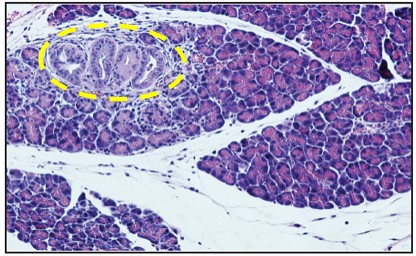

Title: Pre-cancerous lesion

Description: Pancreas sections from control and P. gingivalis-infected mice. Control mouse showing a small pre-cancerous lesion (marked in yellow)